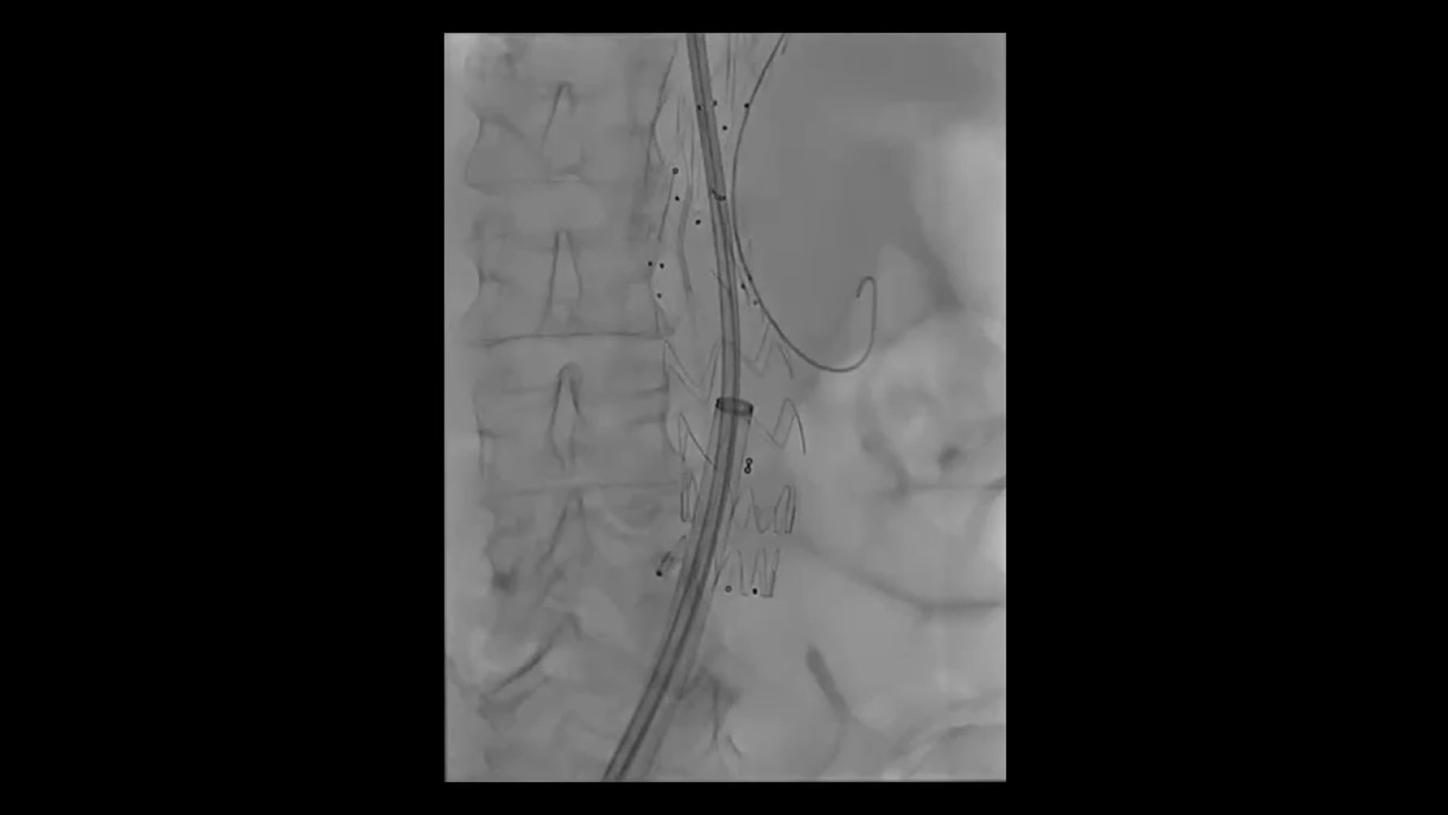

During minimally invasive procedures, it is critical to have a clear view of anatomies and devices. Yet complex imaging tasks or challenging patient conditions often impact image quality. OPTIQ AI delivers constant image quality1 defined by CNR in support of the ALARA principle, independent of patient or C-arm angulation. On top, an AI-powered algorithm reduces image noise in real time across different 2D imaging modes.

Make AI-powered imaging and clear insights your standard during interventions – with OPTIQ AI.

Future-focused IR imaging for a broad procedure mix

Discover how leading clinicians are transforming interventional radiology with Siemens Healthineers technologies. From ultra-fast 3D imaging to laser-guided needle procedures, the ARTIS icono ceiling powered by OPTIQ and syngo DynaCT are redefining what’s possible in IR. Explore real-world cases, expert insights, and the future of image-guided therapy.